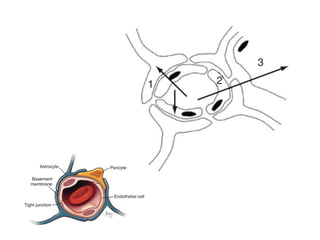

The Blood-Brain Barrier

• Blood-Brain barrier (BBB) is exceptionally active

system

• Endothelial cells can inactivate neuroactivate or

neurotoxic substances

• Regulate microenvironment of the brain, fluid and

ions between circulation and brain

• Interstitial fluid of the brain

• lower Ca2+ and K+ and higher Mg2+

• Blood-Brain barrier(BBB) is exceptionally active system • Endothelial cells can inactivate neuroactivate or neurotoxic substances • Regulate microenvironment of the brain, fluid and ions between circulation and brain • Interstitial fluid of the brain • lower Ca2+ and K+ and higher Mg2+